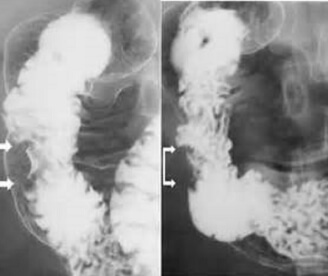

Більшість хвороб можуть призвести до смерті, тому боятися лише раку – це неприпустима помилка. Подивіться знімки органів людей, у яких все почалося з неприємного запаху з рота, сверблячки та кров'янистих виділень із анального отвору відповідно, а закінчилося доповіддю патологоанатома.